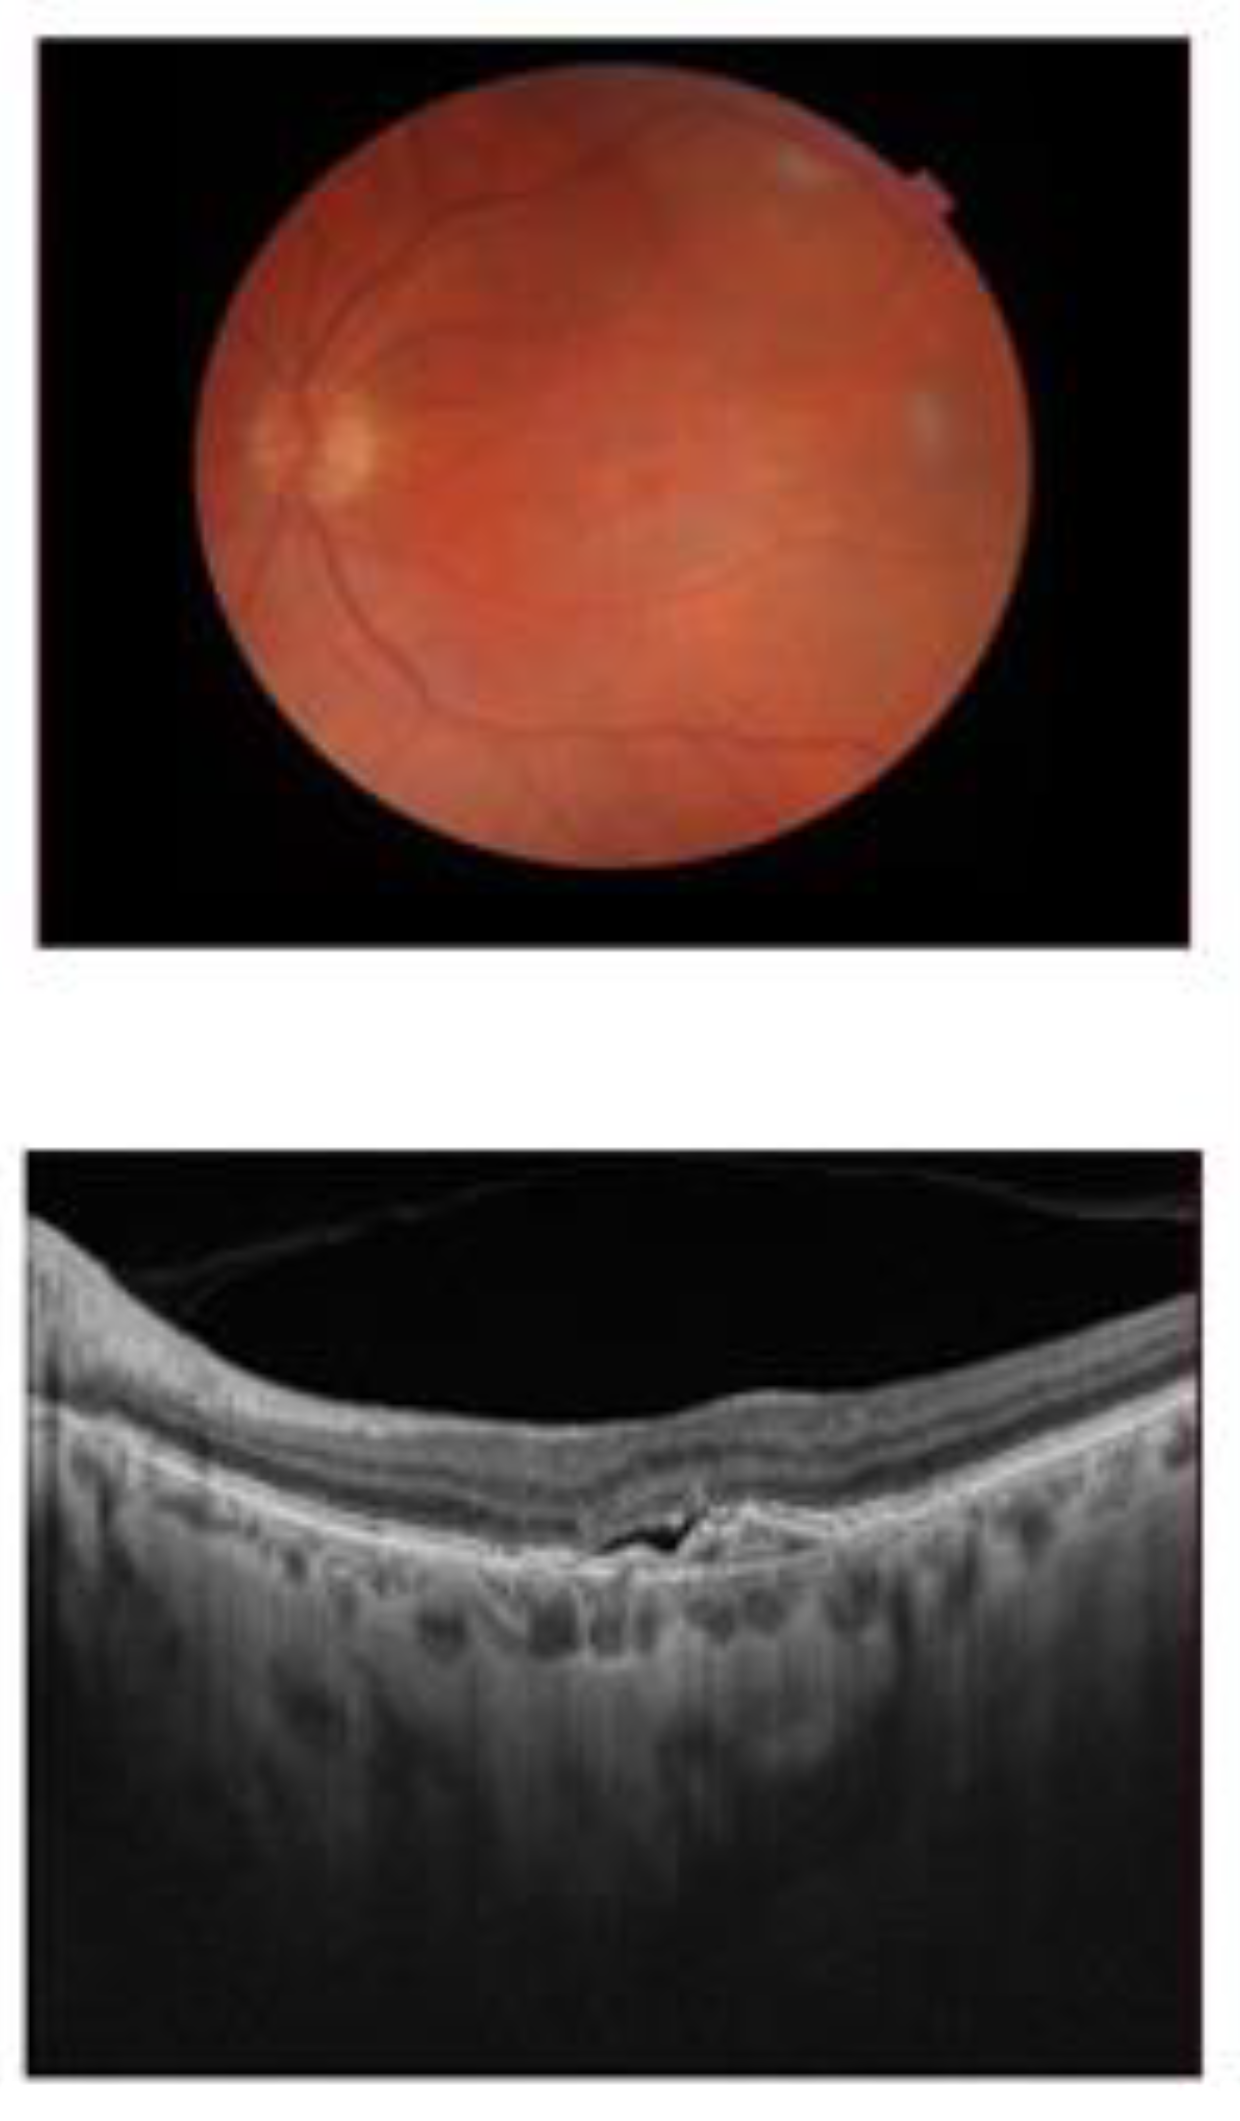

4.3. Ophthalmological Evaluation

4.4.2. Exudative AMD Response to Anti-VEGF Injection Treatment